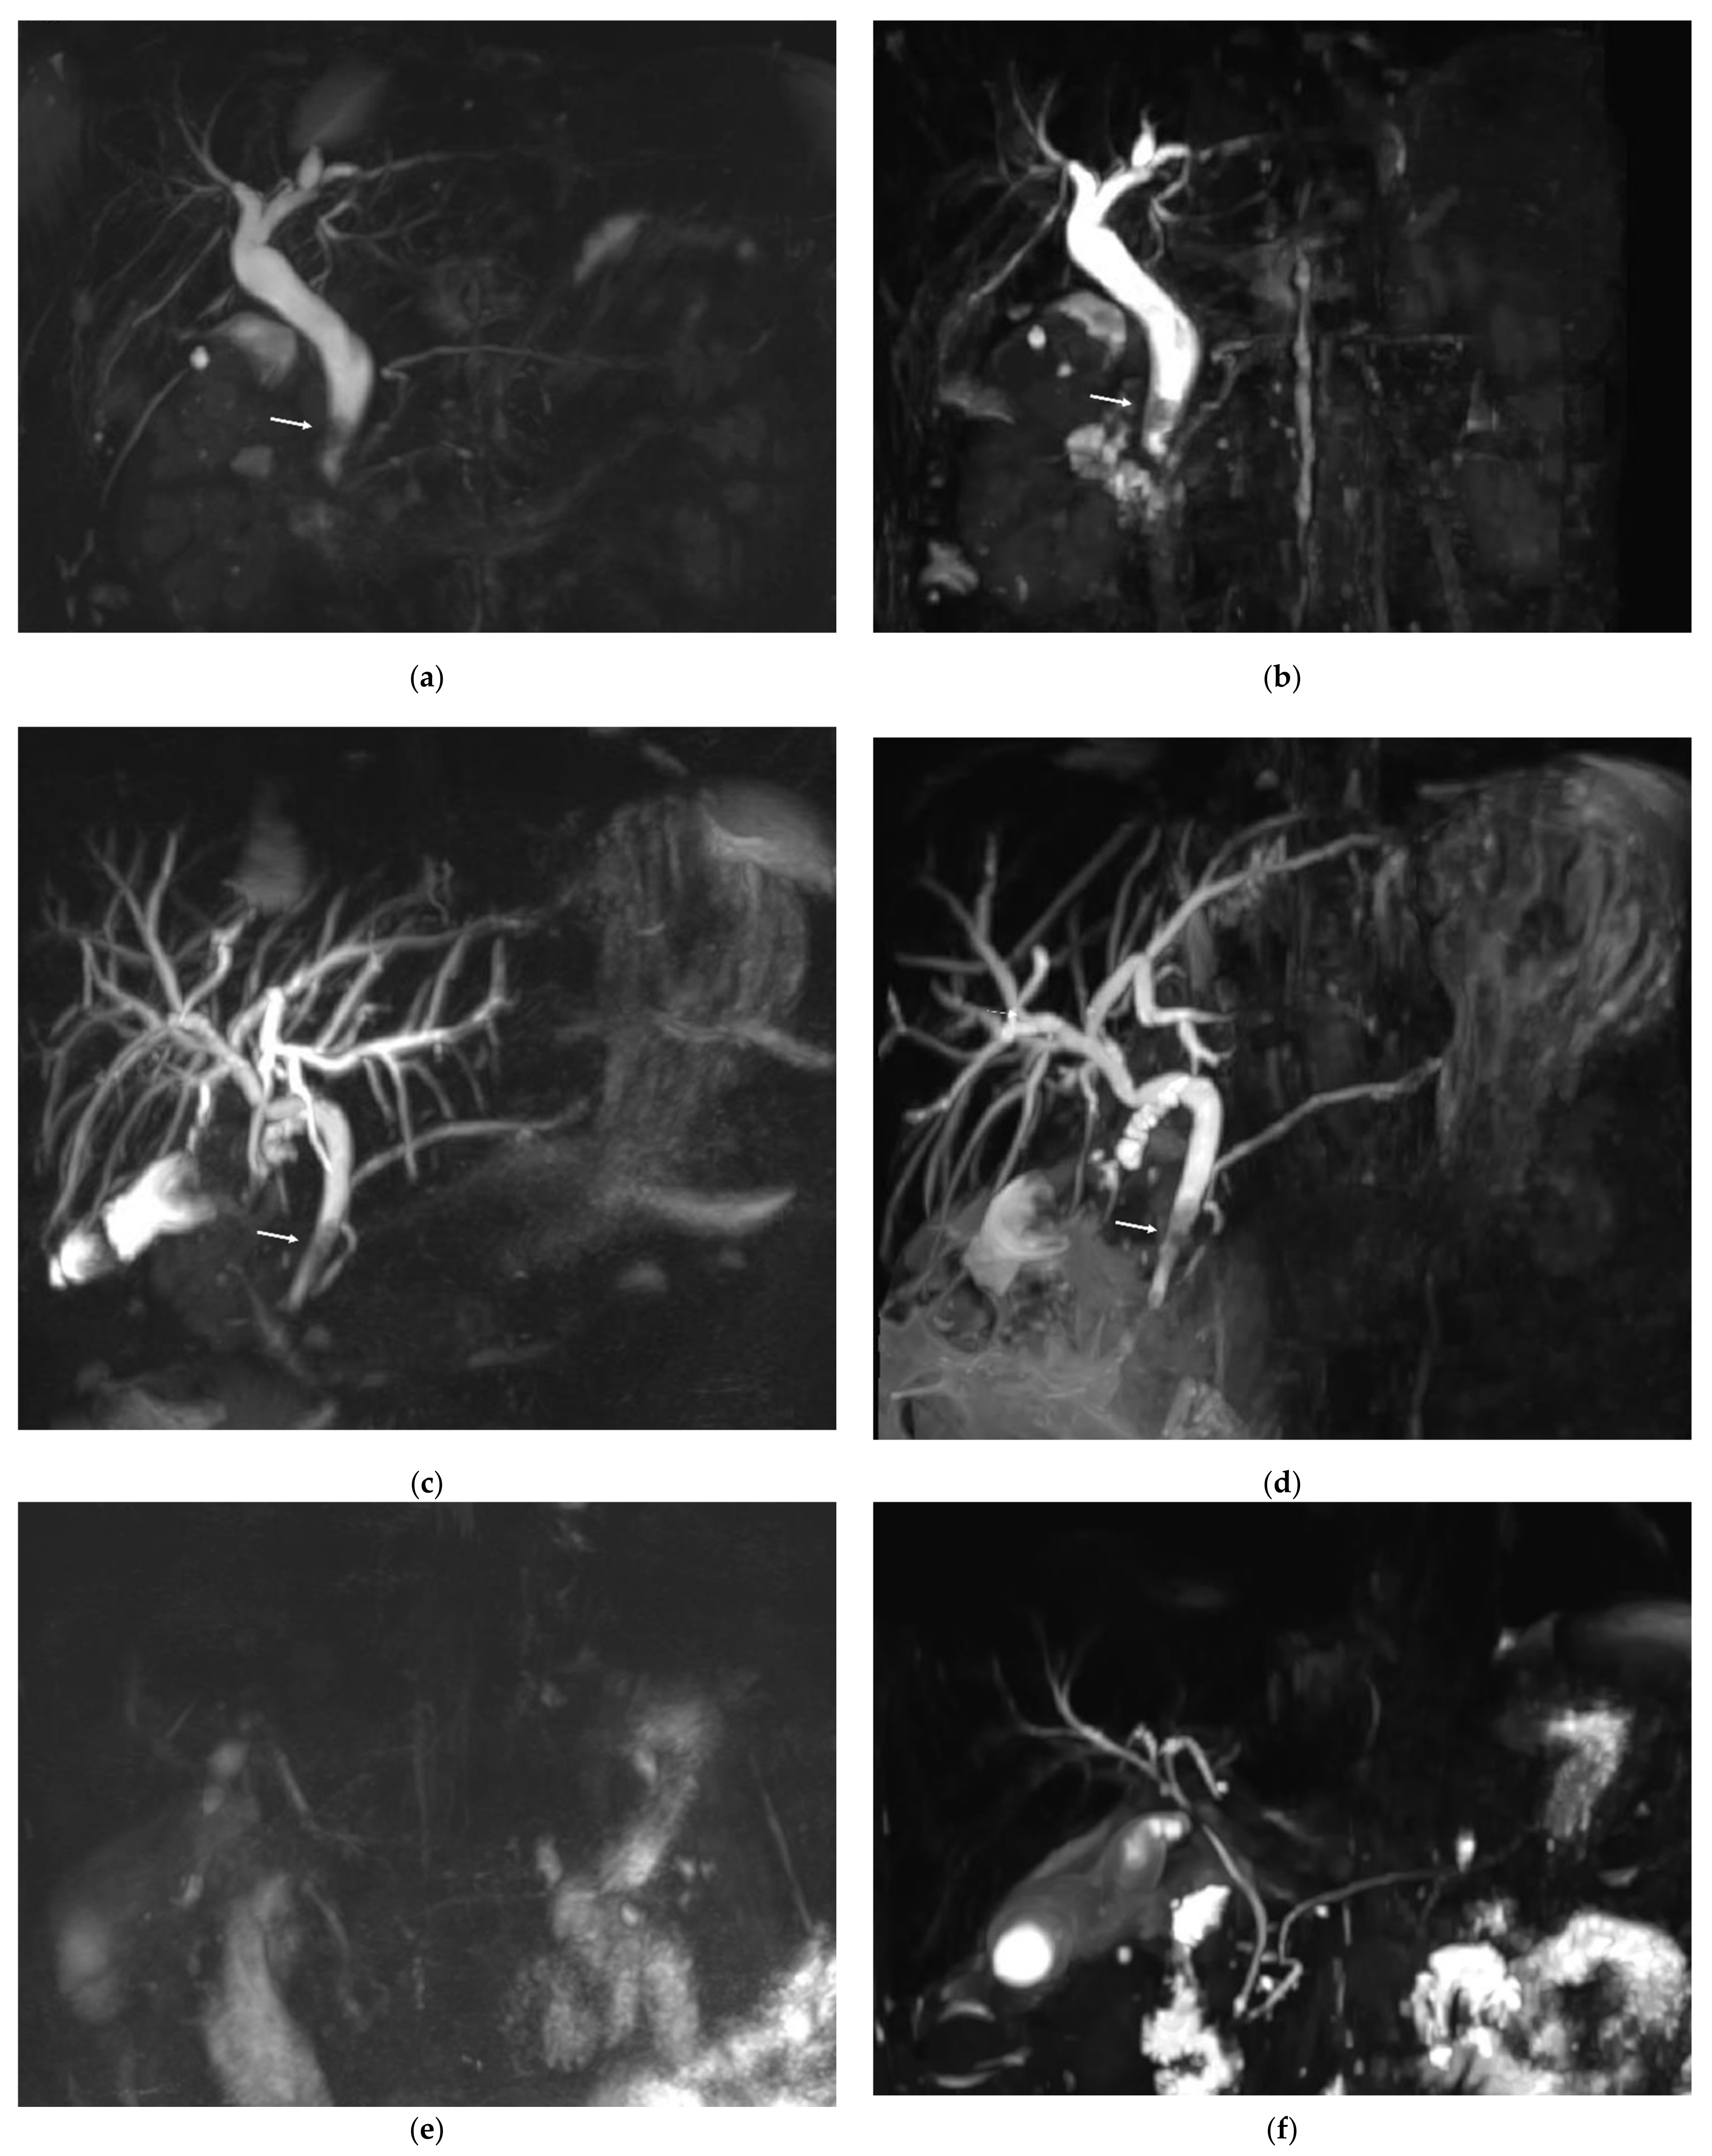

Figure 3 shows example MRCP images obtained with RT-MRCP and CS-BH-MRCP sequences with their qualitative image-quality criteria scorings.

Figure 3.

Example of MRCP images obtained with RT-MRCP and CS-BH-MRCP sequences: (a,b) MRCP was performed in this 69-year-old female with chronic cholecystitis for suspected choledocholithiasis. The motion artefacts noted on the RT-MRCP sequence (a) were less noticeable on the CS-BH-MRCP sequence (b). Note that qualitative image-quality criteria were assessed on native images, whereas MIP images are shown on this figure. (a) For RT-MRCP, qualitative image-quality criteria were scored by senior radiologist, as follows: overall image quality: 3; presence of artefacts: 3; background suppression: 3; distal CBP visualization: 3; proximal CBD visualization: 4; cystic duct confluence: 3; right primary IHBD visualization: 3; left primary IHBD: 3; right anterior sectoral duct: 2; right posterior sectoral duct: 2; left medial duct: 2; left lateral duct: 3; distal and central MDP: 3; proximal MDP: 2. (b) For CS-BH-MRCP qualitative image-quality criteria were scored by senior radiologist as follows: overall image quality: 5; presence of artefacts: 4; background suppression: 4; distal CBP visualization: 4; proximal CBD visualization: 5; cystic duct confluence: 5; right primary IHBD visualization: 5; left primary IHBD: 5; right anterior sectoral duct: 5; right posterior sectoral duct: 5; left medial duct: 5; left lateral duct: 5; distal and central MDP: 5; proximal MDP: 4. RT-MRCP acquisition time was 5 min 5 s.

Based on the consensus between the two readers, CBD lithiasis was present in 10 of the 54 patients. In three patients, the calculi were visible on both MRCP sequences and on a non-MRCP sequence and confirmed by ERCP. In five patients, CBD lithiasis was visible on the RT-MRCP sequence and on a non-MRCP sequence but not on the CS-BH-MRCP sequence. Among these five patients, only one had calculi visible by ERCP and three had uninterpretable CS-BH-MRCP images (diagnostic confidence of 1). Finally, in two patients, calculi were visible on the CS-BH-MRCP sequence and on non-MRCP sequences but not on the RT-MRCP sequence. Among these two patients, only one had calculi visible by ERCP. The RT-MRCP was considered interpretable in both patients. No significant difference was found between the CS-BH-MRCT and RT-MRCP sequences for the detection of bile-duct lithiasis (p = 0.30). One stone was fortuitously discovered in one patient referred for BD-IPMN, only on CS-BH-MRCP sequence (not included in analysis). Figure 4 shows three examples of MRCP images of patients referred for suspected choledocholithiasis using RT-MRCP and CS-BH-MRCP sequences. Appendix A, Table A6 shows the number of CBD lithiasis detection based on the consensus between the two readers with each MRCP sequence and the agreement between the two sequences.

Figure 4.

Three examples of MRCP images of patients referred for suspected choledocholithiasis using RT-MRCP and CS-BH-MRCP sequences. (a,b) MRCP images from a 41-year-old female. The stone within the common bile duct (arrow) was clearly seen with both RT-MRCP (a) and CS-BH-MRCP (b) sequences with a diagnostic confidence score of 3. RT-MRCP acquisition time was 4 min 30 s. (c,d) MRCP images from a 61-year-old female. Both RT-MRCP (c) and CS-BH-MRCP (d) sequences showed intra-hepatic bile duct dilation upstream of calculi (arrows) in the common bile duct with a diagnostic confidence score of 3. RT-MRCP acquisition time was 3 min 23 s. (e,f) MRCP images from a 55-year-old male. (e) RT-MRCP showed very poor image quality and was uninterpretable. The diagnostic confidence was scored 1. (f) CS-BH-MRCP showed better image quality, with a diagnostic confidence score of 2, allowing moderate confidence to diagnose the absence of CBD lithiasis. RT-MRCP acquisition time was 14 min 41 s.